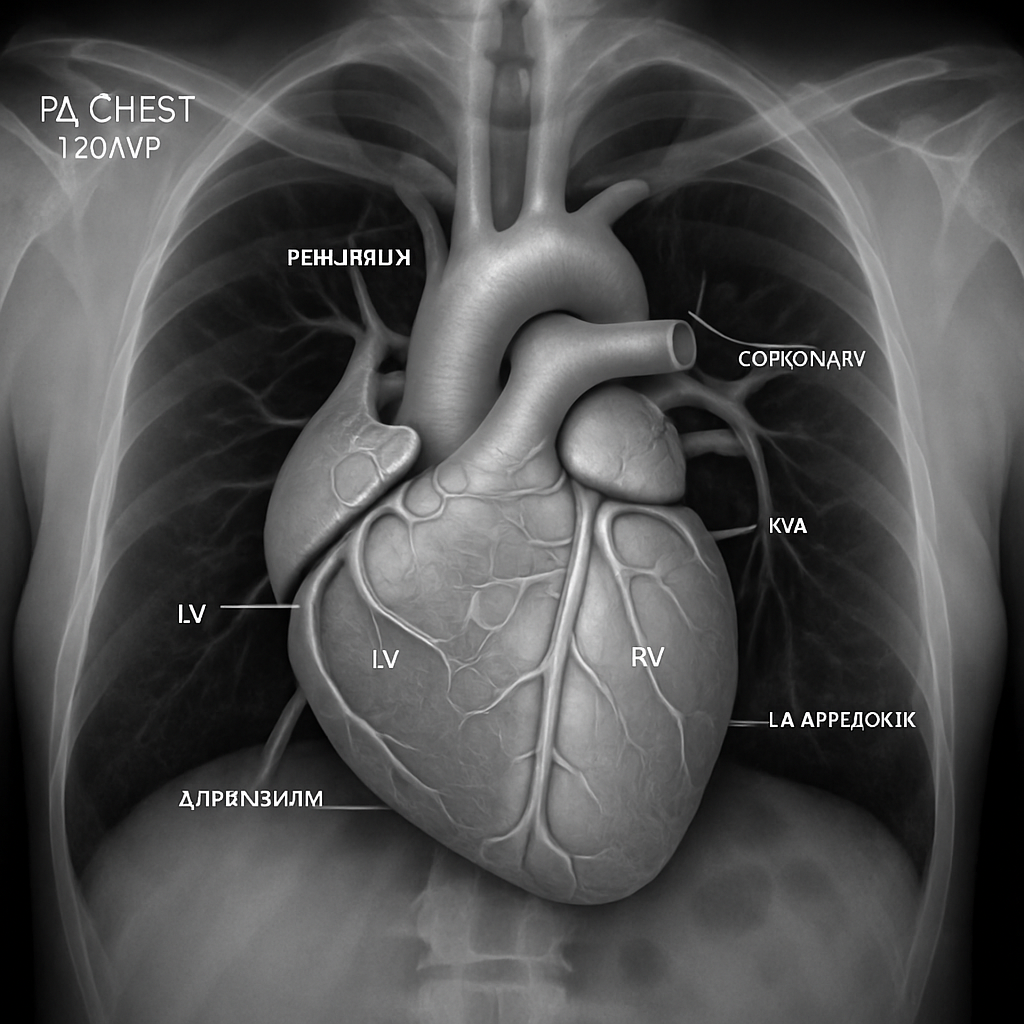

Chest X-ray — PA View (Cardiac Silhouette)

PA chest radiograph focused on the cardiac silhouette showing the normal heart borders. Normal cardiothoracic ratio. Visible structures: right atrial border, left ventricular border, aortic knob, pulmonary artery segment.

DIGITAL RADIOGRAPHY AI Generated 2026-03-16

Pa Chest 120 kVp

Standard PA chest X-ray focused on cardiac silhouette. Normal CTR <0.5. Show aortic knob, PA segment, LA appendage, LV border.

OpenAI gpt-image-1